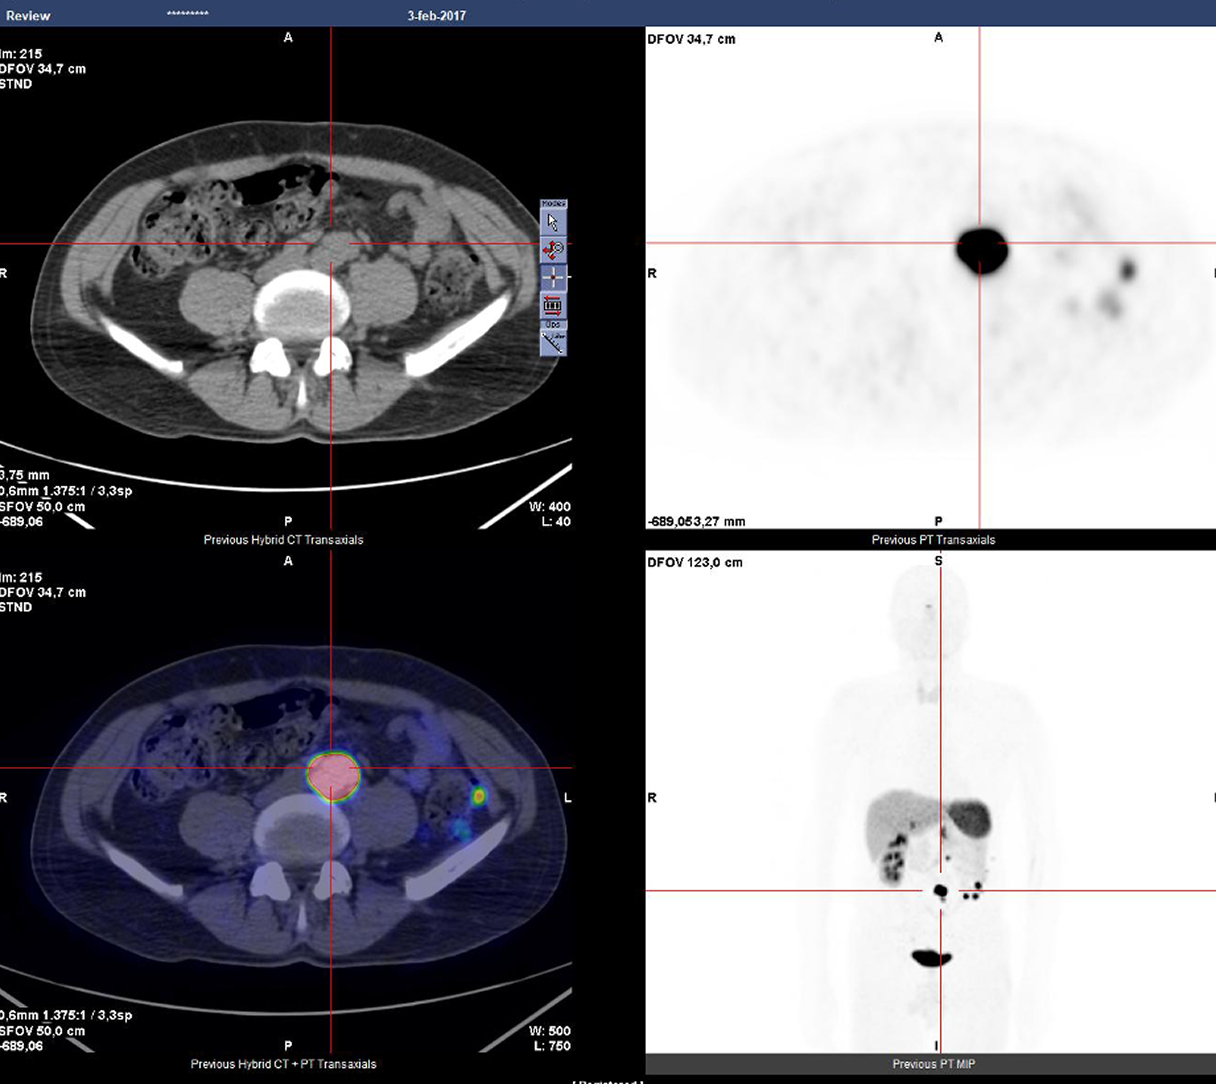

Dentro l'immagine

There is a world outside the stent mesh

Caso condiviso da Saima Mushtaq

Paziente con anamnesi di malattia coronarica e pregresso impianto di stent sulla discendente anteriore sinistra.

Per prima cosa, esamina l'intera scansione. Concentrati sul tronco comune e sulla porzione prossimale della discendente anteriore sinistra.

Fifty shades of grey

Caso condiviso da Marcello De Santis